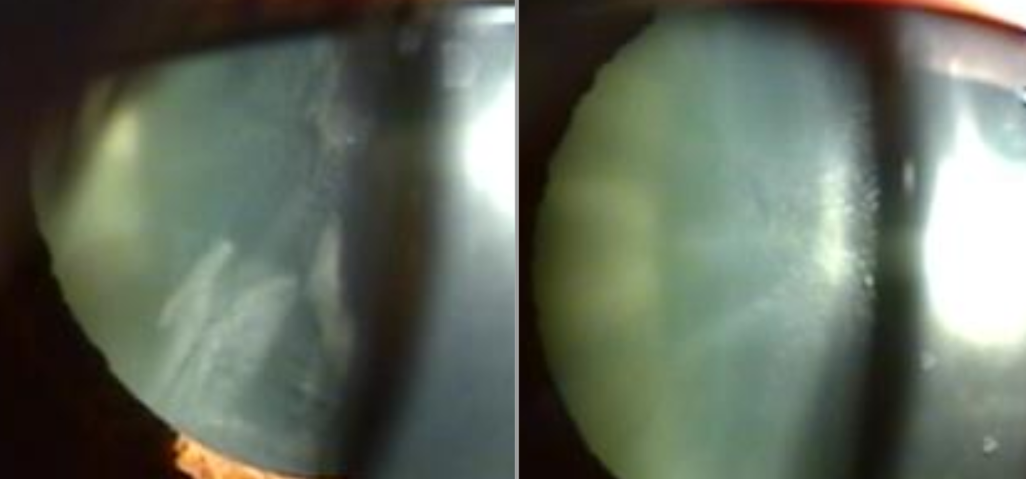

- 소수성 코팅: 후낭혼탁(PCO, posterior capsule opacification) 발생을 억제하여 장기적인 투명성을 유지합니다.

본 증례에서도 1년 6개월 동안 PCO 발생 없이 안정적인 시력을 유지하며, 근거리 작업이 많은 환자의 요구를 충족하였습니다.